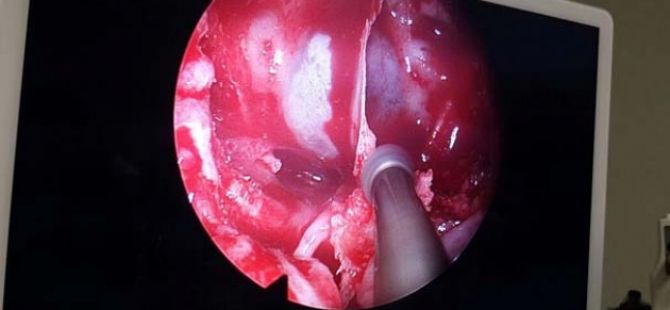

Tuvalete sık gitme hissi ciddi bir sorunu ortaya çıkardı. Bu sağlık sorunu sizinde başınıza gelebilir.